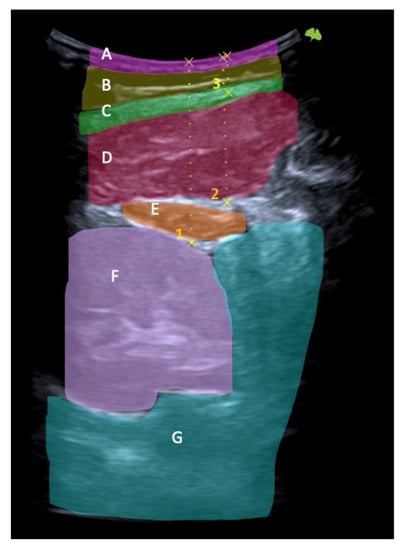

First, the last lumbar vertebra and the first sacral vertebra were located, and from there, the spinous processes of L4 and L2 were marked and assessed using ultrasonography. At the level of L2, the spinous process is located in the short axis, and the probe was moved to the right or left lateral side depending on randomization. We visualized the skin and the fatty tissue, we left the longissimus muscle towards the medial side, and we placed the iliocostalis lumborum muscle in the long axis, as well as the quadratus lumborum and the kidney, in the center of the screen. We asked the subjects to breathe in to see how the kidney descended and became more visible. When in maximum inspiration, we froze the image to make the following measurements: skin-upper edge of the iliocostalis lumborum muscle, skin-lower edge of the iliocostalis lumborum muscle, and skin-kidney. Then, a different researcher placed two fingers exerting pressure, as if it were the “tissue depression prior to performing the DP”. More ultrasound gel was placed between the fingers, and the sonographer placed the probe again in the short axis. An inspiration was requested to freeze the image and perform the same measurements mentioned above. At L4 level, the same protocol was followed with the difference in that, instead of performing the last skin-kidney measurement, the skin-peritoneum measurement was performed. The measurements were made on the right and left sides and with and without compression (Figure 3, Figure 4 and Figure 5).

Figure 5. Ultrasonography image. Long-axis measurements in L2 level, left side at rest. Skin-kidney (1), skin-iliocostalis lumborum bottom edge (2), and skin-iliocostalis lumborum top edge (3) with the finger’s acoustic shadow painted (orange) (A). Moment of the sampling technique (B).